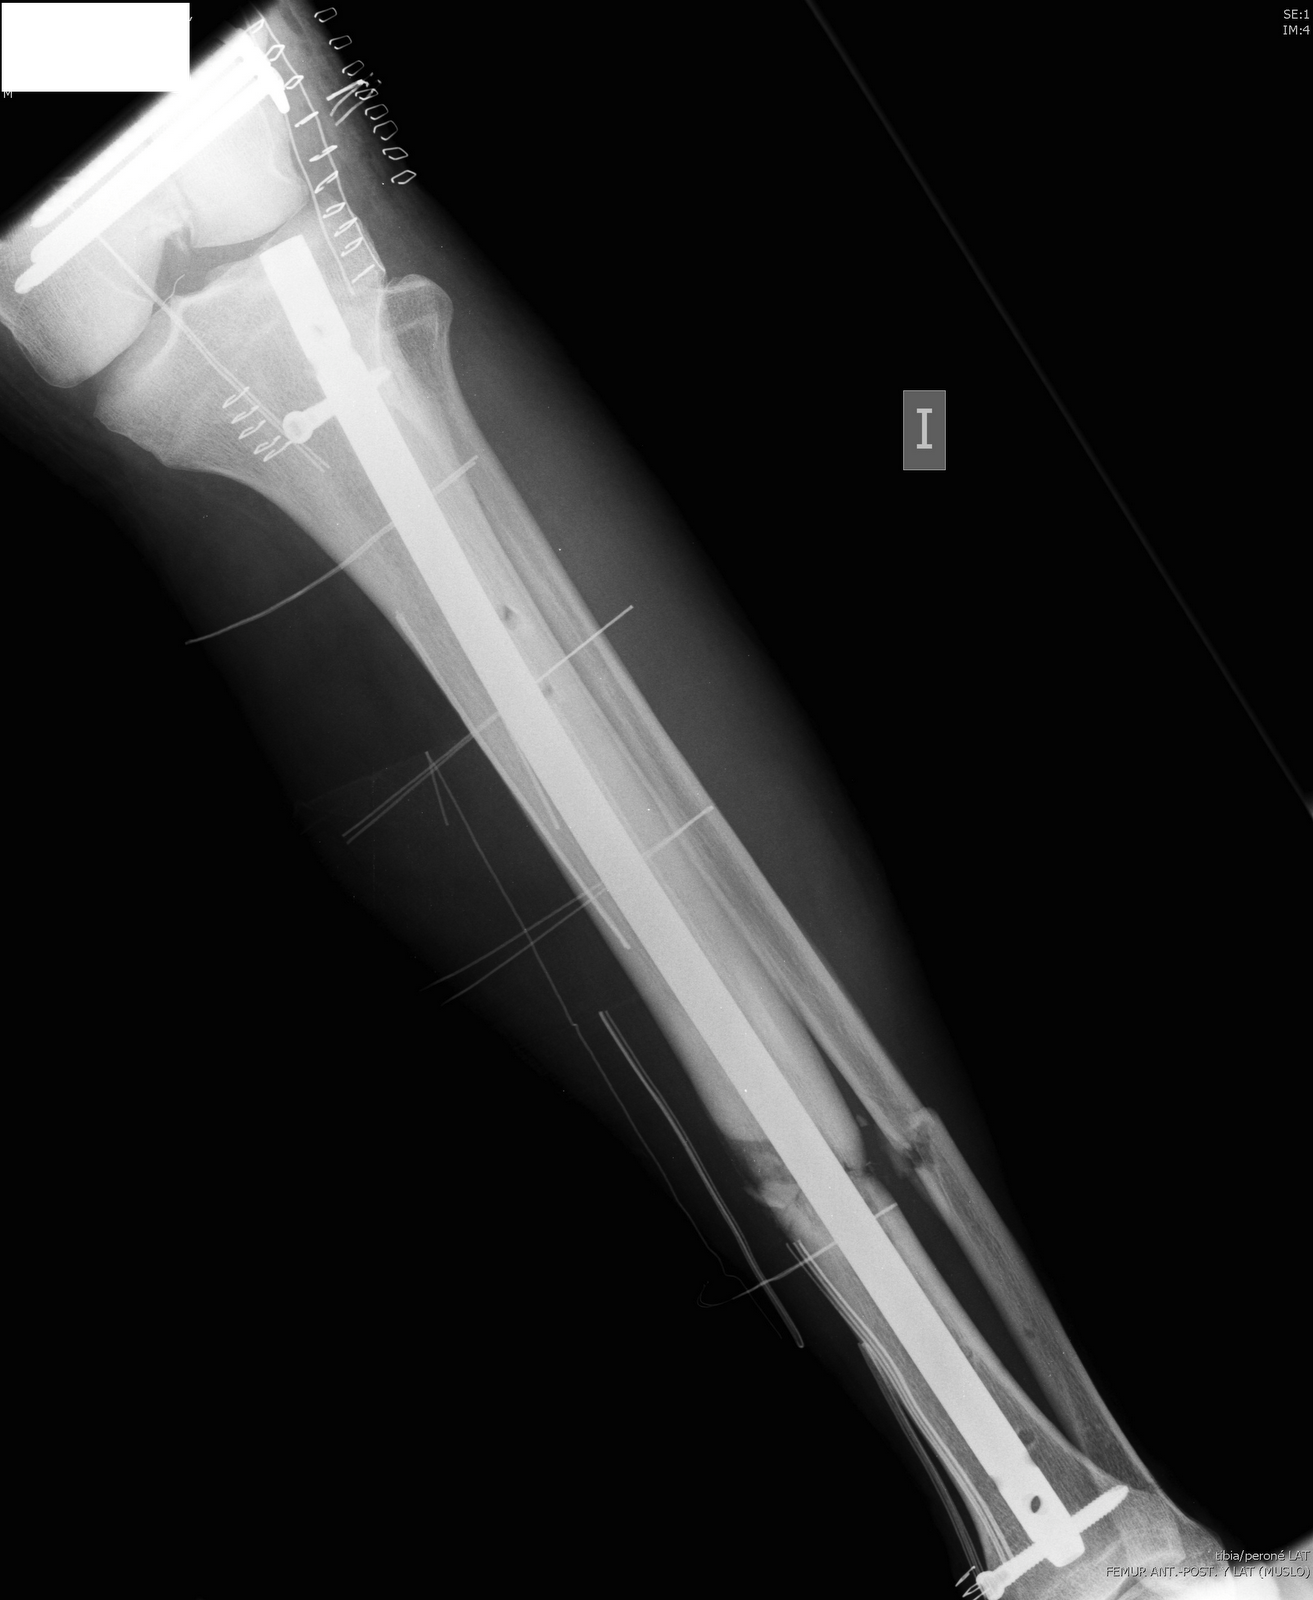

Fractura de la tibia, tratamiento, cirugรญa y tiempo de recuperacion

ยฟQue es un Clavo Bloqueado o Clavo Intramedular?

Tratamiento de fractura de tibia y perone en niรฑos y adultos

Artrodesis tibiotalocalcรกnea con clavo retrรณgrado asistida por …

Clavo tibiotalocalcรกneo en el tratamiento de fracturas osteoporรณticas …

CLAVOS INTRAMEDULARES

CLAVO PARA HUESOS PARA EL TRATAMIENTO DE FRACTURAS.

Uso del clavo intramedular acerrojado retrรณgrado en fรฉmur